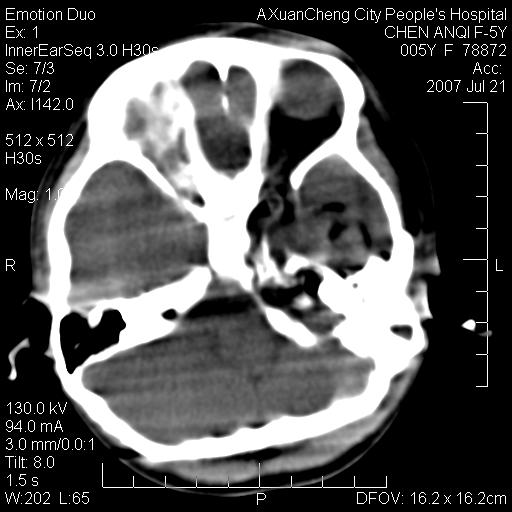

标题: PED0273:5岁,左耳流脓痛疼一周,颅底骨质破坏 [打印本页]

标题: PED0273:5岁,左耳流脓痛疼一周,颅底骨质破坏

患儿5岁,左耳流脓痛疼一周,左外耳道肉芽组织填塞 软组织窗显示病灶内结节状低密度影为气体密度

1.左耳中耳炎. 2.考虑伴颅内感染.

颅底骨质破坏,建议增强扫描

左侧中耳炎并胆脂瘤,左颞骨岩部骨质破坏并颅内感染积气。